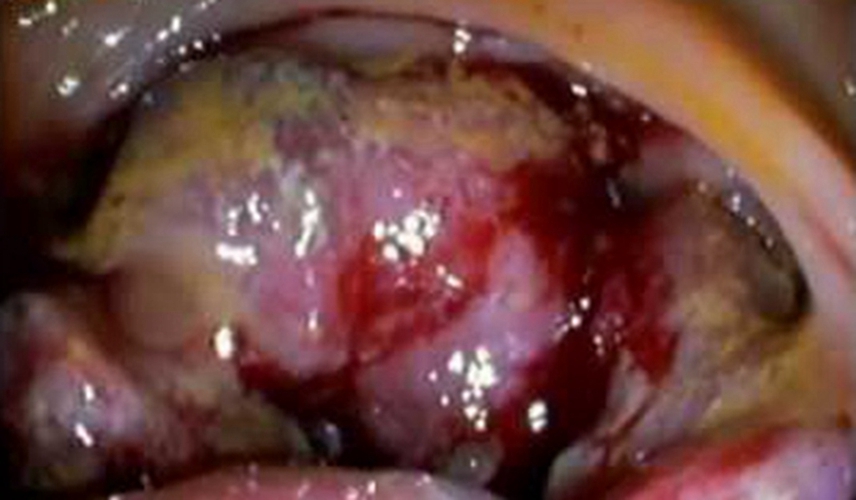

右半結腸癌潰瘍型常見臨床 特點

乙狀結腸癌潰瘍型症狀